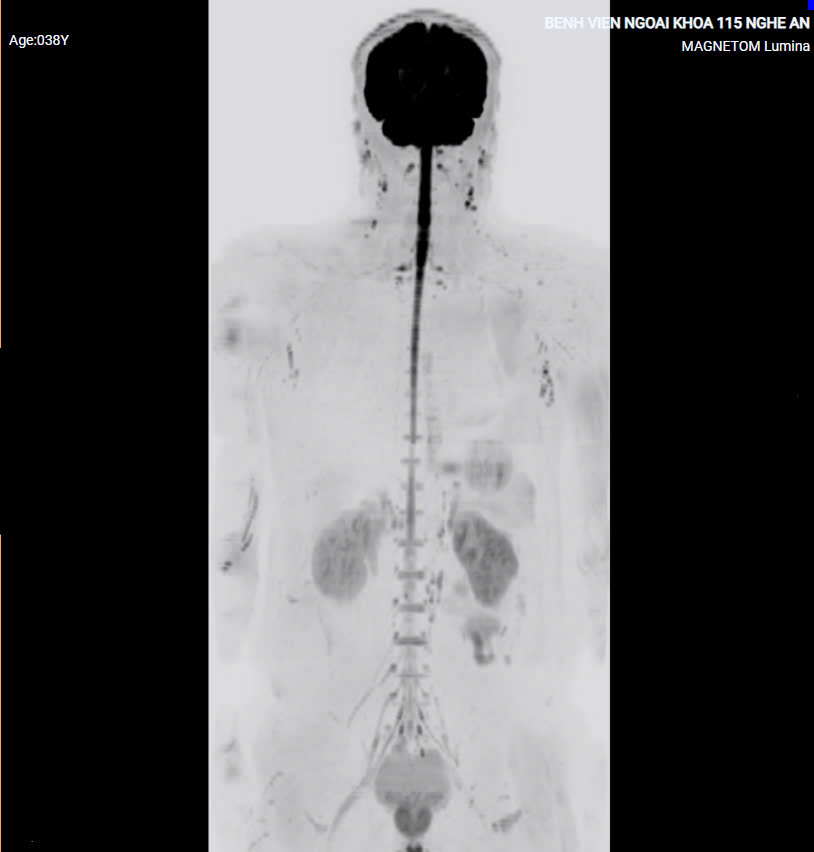

2. Chụp cộng hưởng từ khuếch tán toàn thân

- Cộng hưởng từ khuếch tán toàn thân (tiếng Anh viết tắt là DWIBS – Diffusion-weighted Whole body Imaging with Background Suppression) là kỹ thuật chụp cộng hưởng từ khuếch tán toàn thân xóa nền.

- Người bệnh trong trường hợp này có thể thở bình thường, là một ưu điểm so với các chuỗi xung khác của kỹ thuật chụp cộng hưởng từ. Kỹ thuật DWIBS cho phép cắt các lớp mỏng, từ đó cho phép ta tái tạo hình ảnh ba chiều MPR và MIP, vì vậy sẽ cho hình ảnh giống với hình ảnh chụp PET-CT.

- Hiện nay phương pháp chụp DWIBS là phương pháp có thể được sử dụng để thay thế chụp PET-CT(là phương pháp có sử dụng dược chất phóng xạ và tia X), người bệnh sẽ không phải chịu ảnh hưởng của dược chất phóng xạ và tia xạ, vì vậy phương pháp DWIBS là phương pháp được ưu tiên lựa chọn để chẩn đoán sớm các ung thư nguyên phát, thứ phát, hạch bạch huyết và theo dõi sự tiến triển của các khối u.

- Ngoài ưu thế của DWIBS trong chẩn đoán sớm ung thư, thì DWIBS còn có ý nghĩa trong chẩn đoán các bệnh lý áp xe và các tổn thương bệnh lý khác của các cơ quan trong cơ thể.